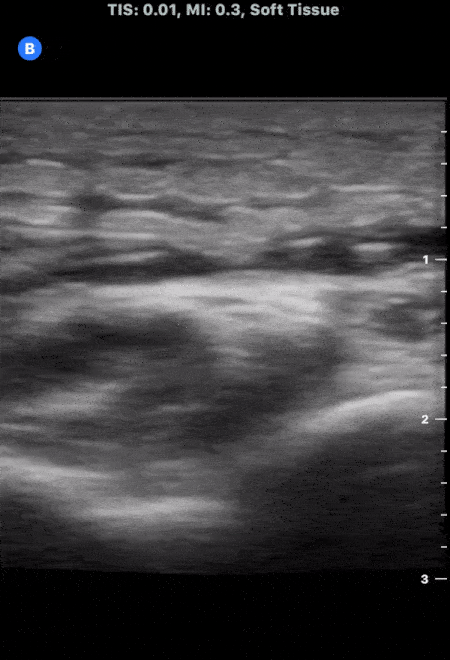

This image demonstrates the common finding of cobblestoning seen in cellulitis. Note the anechoic areas surrounding islands of subcutaneous tissue. Michael Macias, MD